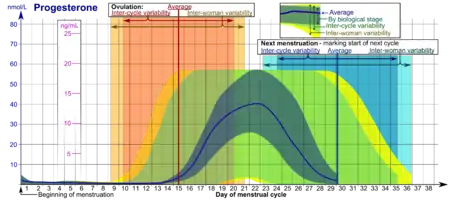

Concentración

En las mujeres, la concentración de progesterona es relativamente baja durante la fase preovulatoria del ciclo menstrual, sube después de la ovulación y se mantiene elevada durante la fase lútea, como muestra el diagrama. La concentración de progesterona tiende a ser <2 ng/ml antes de la ovulación y >5 ng/ml después de la ovulación. En el embarazo la concentración de progesterona se mantiene inicialmente en valores lúteos. Con el inicio del cambio lúteo-placentario en el embarazo la concentración empieza a subir y puede alcanzar los 100 o 200 ng/ml al término del embarazo. Se ha discutido si una disminución de progesterona es o no fundamental para la iniciación del parto y puede que esto sea dieferente entre especies. Después del parto y durante la lactancia la concentración de progesterona es muy baja.

La concentración de progesterona es relativamente baja en niños y en mujeres posmenopáusicas.[19] Los varones adultos muestran valores similares a los de la fase folicular del ciclo menstrual en las mujeres.

- Los intervalos marcados By biological stage (por etapas biológicas) pueden ser ocupados en ciclos menstruales en estrecho seguimiento en lo que respecta a otros indicadores de su progreso biológico, con la escala de tiempo comprimida o estirada dependiendo de cuan rápido o lento, respectivamente, sea el progreso del ciclo comparado con un ciclo promedio.

- Los intervalos etiquetados Inter-cycle variability (variabilidad inter-ciclo) son más apropiados para usarse en ciclos no monitoreados donde solo se conoce el comienzo del ciclo y la mujer sabe la duración promedio de su ciclo y tiempo de ovulación, y que son relativamente regulares, con la escala de tiempo comprimida o estirada dependiendo de cuan corto o largo, respectivamente, sea el ciclo comparado con el promedio de la población.

- Los intervalos marcados Inter-woman variability (variabilidad entre mujeres) son más apropiados para usarse cuando se deconocen la duración y tiempo de ovulación y solo se conoce el comienzo del ciclo.

| Circunstancia | Intervalos de referencia para análisis de sangre | ||

|---|---|---|---|

| Límite inferior | Límite superior | Unidades | |

| Mujer con el ciclo menstrual | (véase el diagrama) | ||

| Mujer posmenopáusica | <0,2[21] | 1[21] | ng/mL |

| <0,6[22] | 3[22] | nmol/L | |

| Mujer que toma anticonceptivos orales | 0,34[21] | 0,92[21] | ng/mL |

| 1,1[22] | 2,9[22] | nmol/L | |

| Varón de 16 años o más | 0,27[21] | 0,9[21] | ng/mL |

| 0,86[22] | 2,9[22] | nmol/L | |

| Mujer o varón entre 1 y 9 años | 0,1[21] | 4,1[21] o 4,5[21] | ng/mL |

| 0,3[22] | 13[22] | nmol/L | |